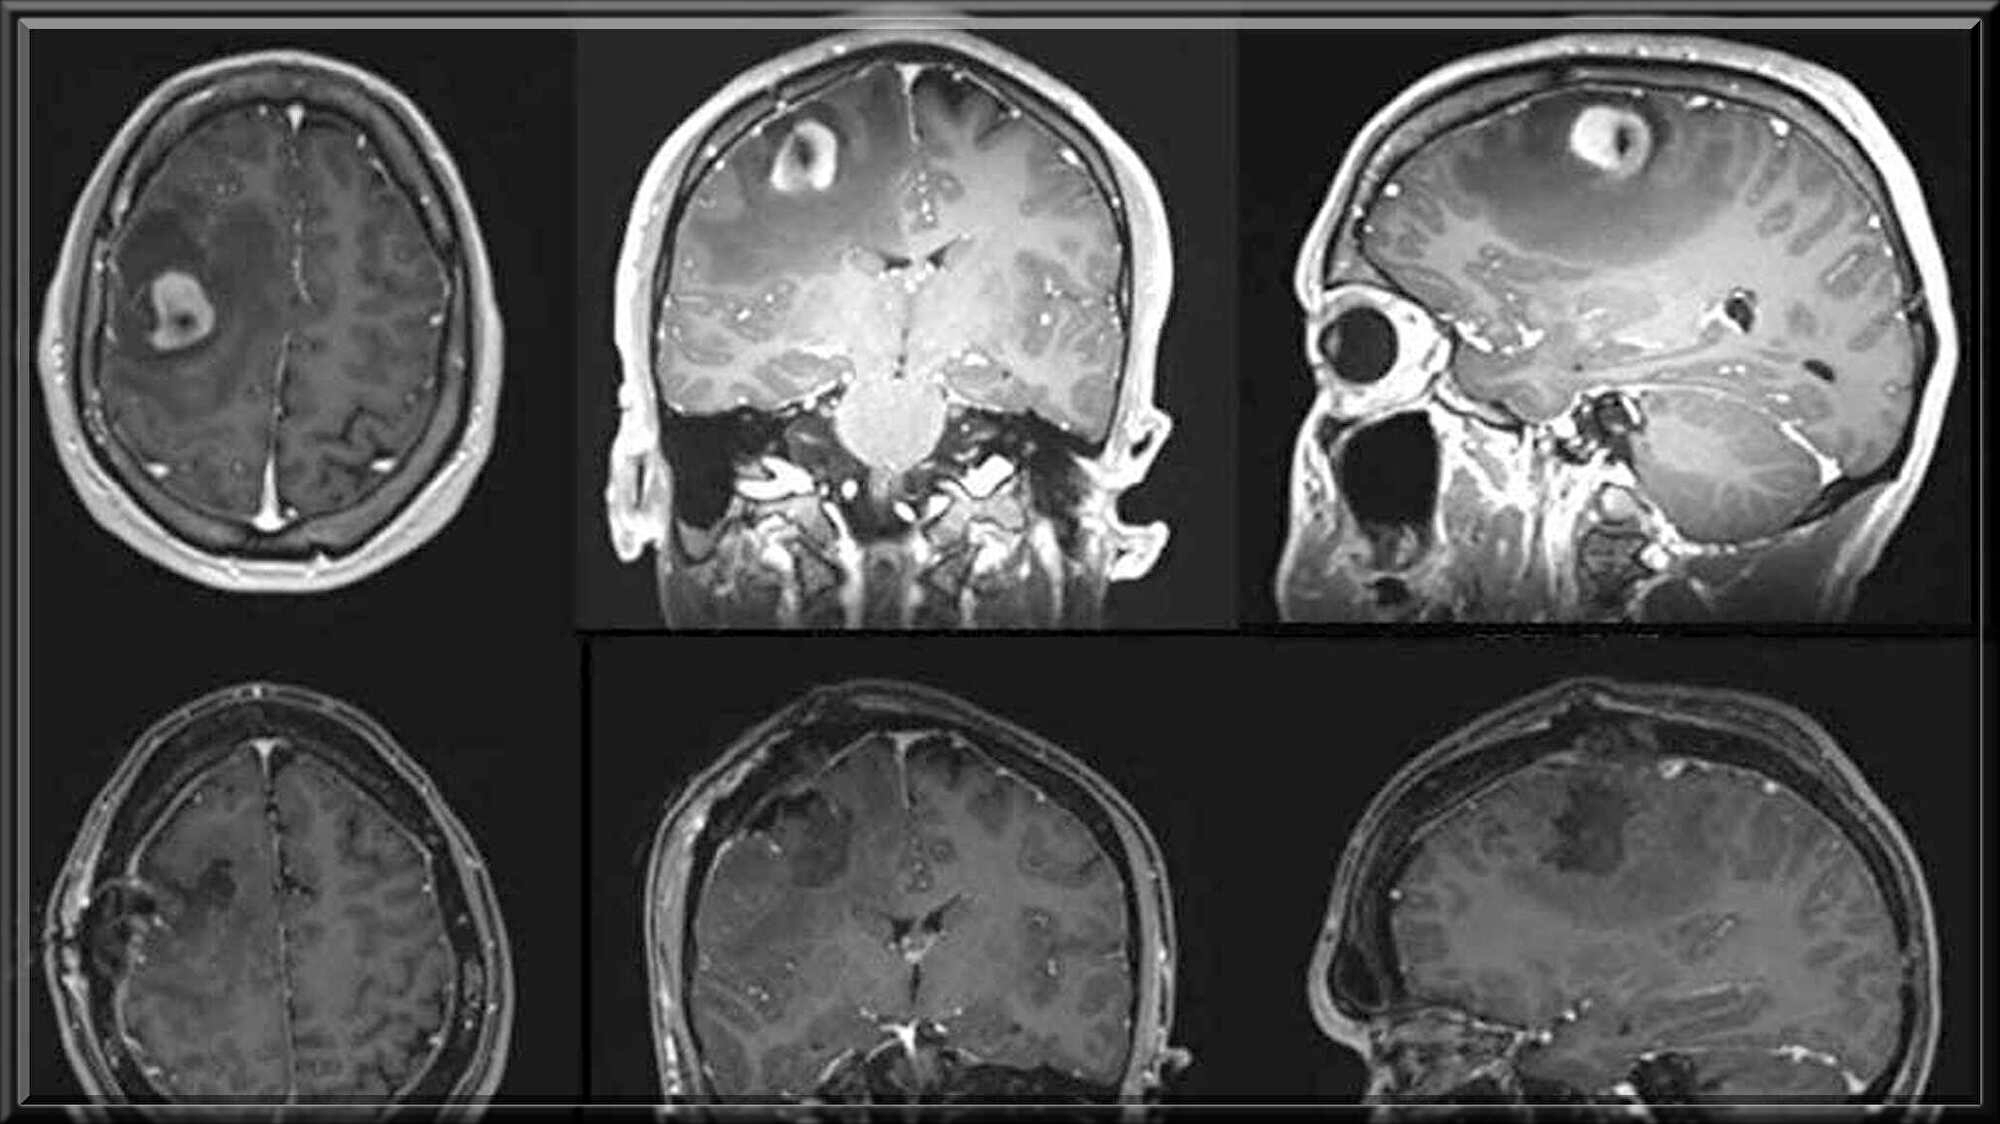

ノーレン氏の右前頭葉に大きな

神経膠腫があるのを発見しました

神経膠腫は神経上皮細胞から発生する

悪性脳腫瘍で右前頭葉は体の左半身の

動きを制御したり発話や言語能力や

その他の認知機能と関連しています